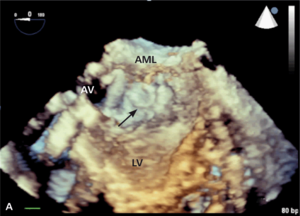

Rycina 1. TEE 3D. Wynik przezskórnego zamknięcia przecieku okołozastawkowego przy protezie uchylno-dyskowej.

Przecieki okołozastawkowe (paravalvular leak, PVL) występują u chorych po implantacji sztucznej zastawki serca, zarówno chirurgicznej, jak i metodą przezskórną lub przezkoniuszkową. W przypadku chirurgicznie implantowanych zastawek są one powikłaniem infekcyjnego zapalenia wsierdzia lub skutkiem poluzowania lub wyprucia fragmentu szwu chirurgicznego albo konsekwencją znacznych zmian typu włóknistego i kalcyfikacji w natywnym pierścieniu zastawkowym, utrudniających prawidłowy kontakt między nim a pierścieniem sztucznej zastawki. Częstość występowania wszystkich (w tym również niewielkich) PVL ocenianych w przezprzełykowym badaniu echokardiograficznym szacuje się na kilkanaście procent u osób po implantacji zastawki aortalnej (aortic valve replacement, AVR) i nieco ponad 20% po implantacji zastawki w pozycji mitralnej (mitral valve replacement, MVR) [1-3]. Według piśmiennictwa kliniczne objawy przecieku okołozastawkowego (niewydolność serca, hemoliza i zwiększone ryzyko wystąpienia infekcyjnego zapalenia wsierdzia) występują u około 1-5% pacjentów po AVR lub MVR [4], przy czym częściej jawne klinicznie są przecieki okołomitralne [5]. Wśród pacjentów z PVL i hemolizą wewnątrznaczyniową należy rozróżnić tych, u których rozpad erytrocytów jest na tyle nasilony, że doprowadza do klinicznie jawnej niedokrwistości, oraz takich, u których przy granicznie małych liczbie czerwonych krwinek i stężeniu hemoglobiny hemolizę wykazać można istotnie zwiększonymi aktywnością LDH, stężeniem bilirubiny pośredniej i haptoglobiny lub zwiększoną liczbą retikulocytów. Diagnostyka obrazowa przecieków okołozastawkowych została szczegółowo omówiona w innych artykułach [6,7]. Leczenie chirurgiczne jest leczeniem z wyboru przy jednoczesnej dysfunkcji zastawki, planowanym jednoczasowym CABG, niestabilności protezy oraz infekcyjnym zapaleniu wsierdzia. W jednej z większych analiz [8] porównujących chorych z PVL leczonych zachowawczo i chirurgicznie wyraźnie udokumentowano korzyść z leczenia zabiegowego (zmniejszenie śmiertelności całkowitej w badanej populacji z 26 do 12%). Alternatywą leczenia chirurgicznego jest przezskórna implantacja zatyczki do kanału przecieku [9]. Wykorzystuje się w tym celu urządzenia dedykowane do zamykania innego typu przecieków wewnątrzsercowych i nieprawidłowych połączeń naczyniowych, jak okludery do zaopatrywania ubytków przegrody międzykomorowej (ventricular septal defect, VSD) czy przetrwałego przewodu tętniczego (patent ductus arteriosus, PDA) lub korki naczyniowe typu Amplatzer vascular plug (AVP, St. Jude Medical). W ośrodku autorów najczęściej wykorzystuje się podczas tych zabiegów korki naczyniowe typu AVP III. Charakteryzują się one spłaszczonym kształtem, co ułatwia ich dopasowanie do zwykle szczelinowatego kształtu przecieku okołozastawkowego. W przypadku przecieków okołomitralnych, szczególnie dostępnych od strony lewego przedsionka lub o znacznych rozmiarach, korzystne może być dojście od strony koniuszka lewej komory serca [10]. Często w zabiegach tych wykorzystuje się więcej niż jedną zatyczkę (ryc. 1).